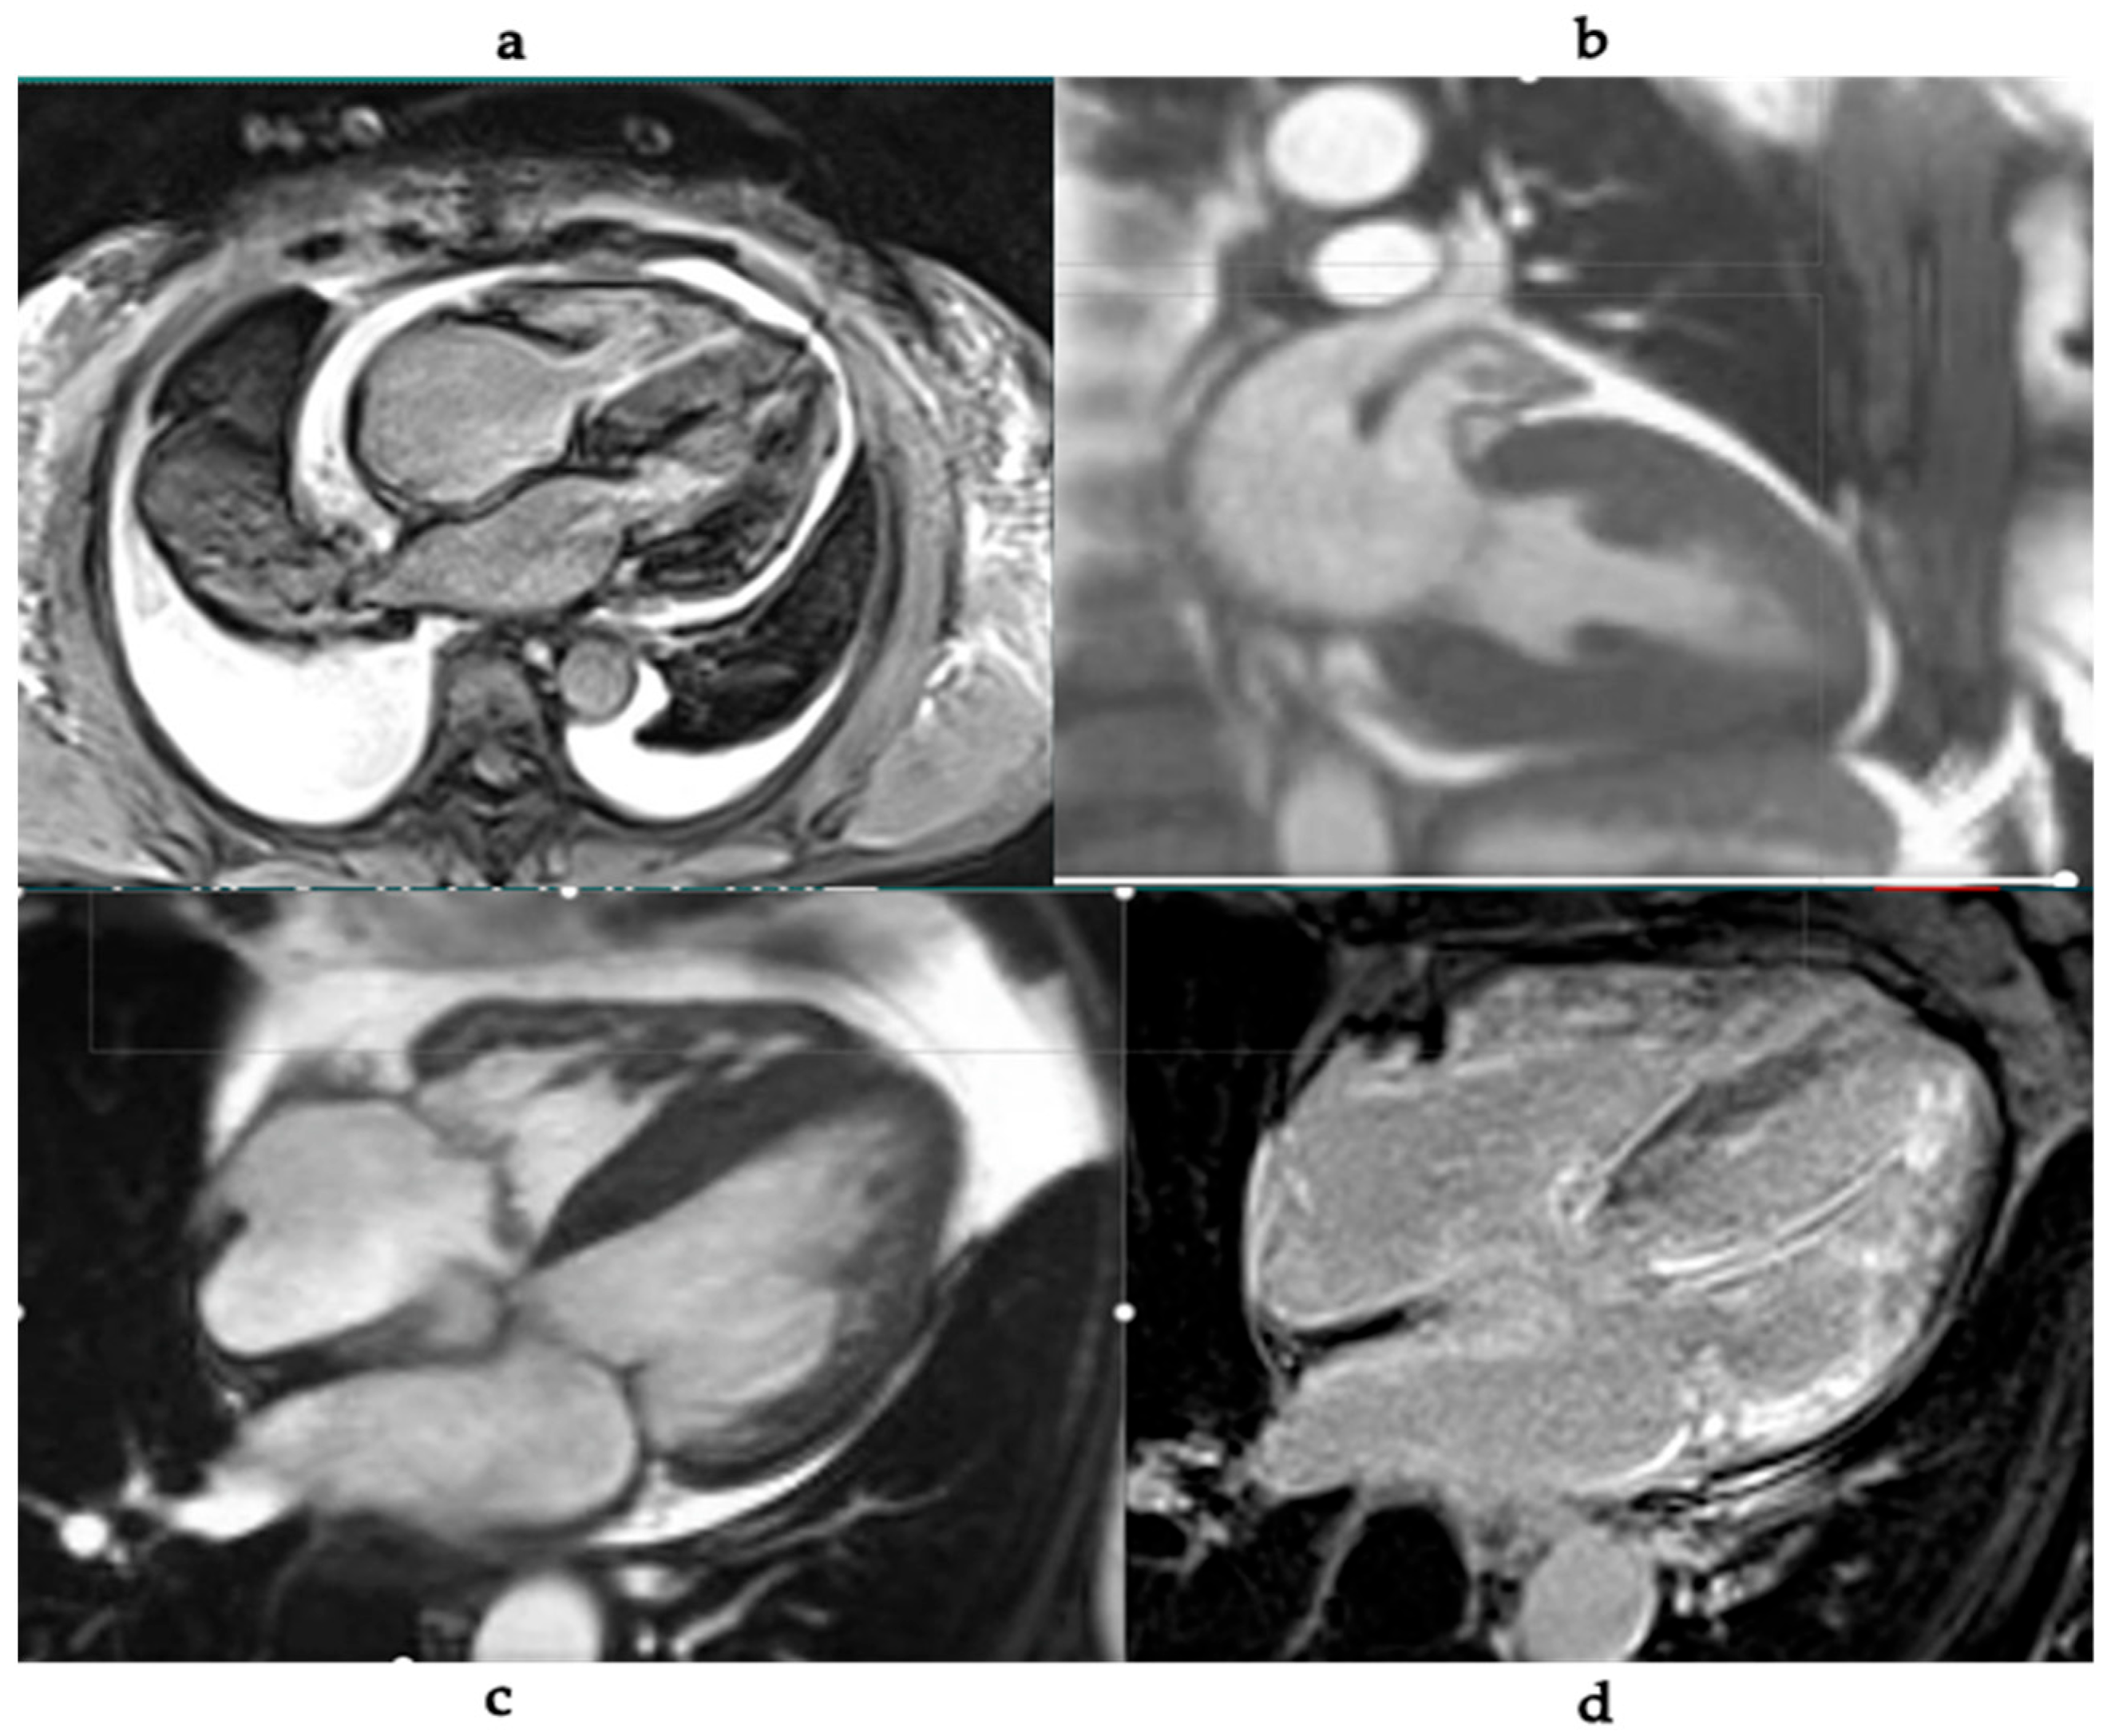

5. Cardiac MRI in Cardiac Amyloidosis

- Increased LV wall thickness and biatrial enlargement.

- Abnormal myocardial nulling pattern on late gadolinium enhancement (LGE).

- Diffuse subendocardial or transmural LGE patterns.

- Elevated native T1 values and increased extracellular volume (ECV) fraction.

| Cardiac MRI (CMR) | - LGE (subendocardial/transmural)- T1/T2 mapping- ECV quantification- Detection of thrombi, effusions | - Excellent tissue characterization- Staging and prognosis- Quantitative assessment of amyloid burden | - Gadolinium contraindicated in advanced CKD- Cost and availability |